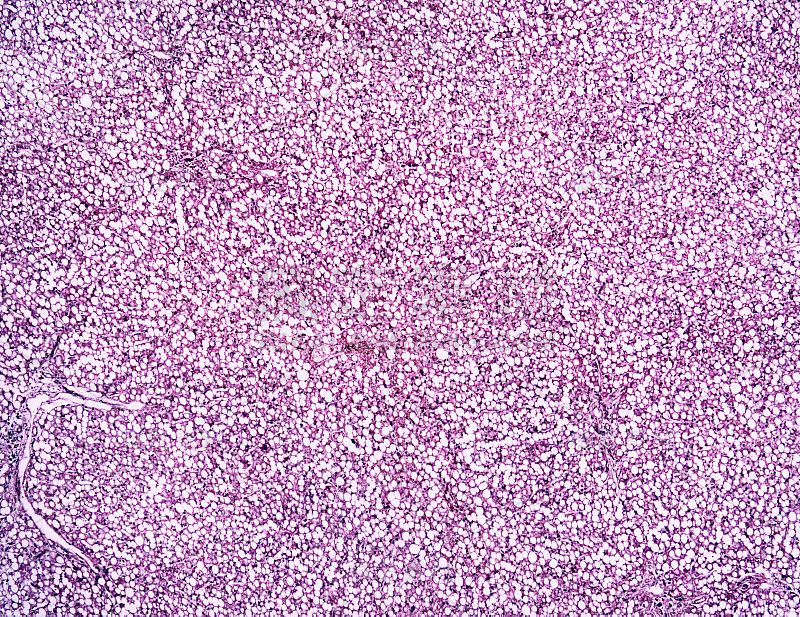

在显微镜下观察肝脏详情